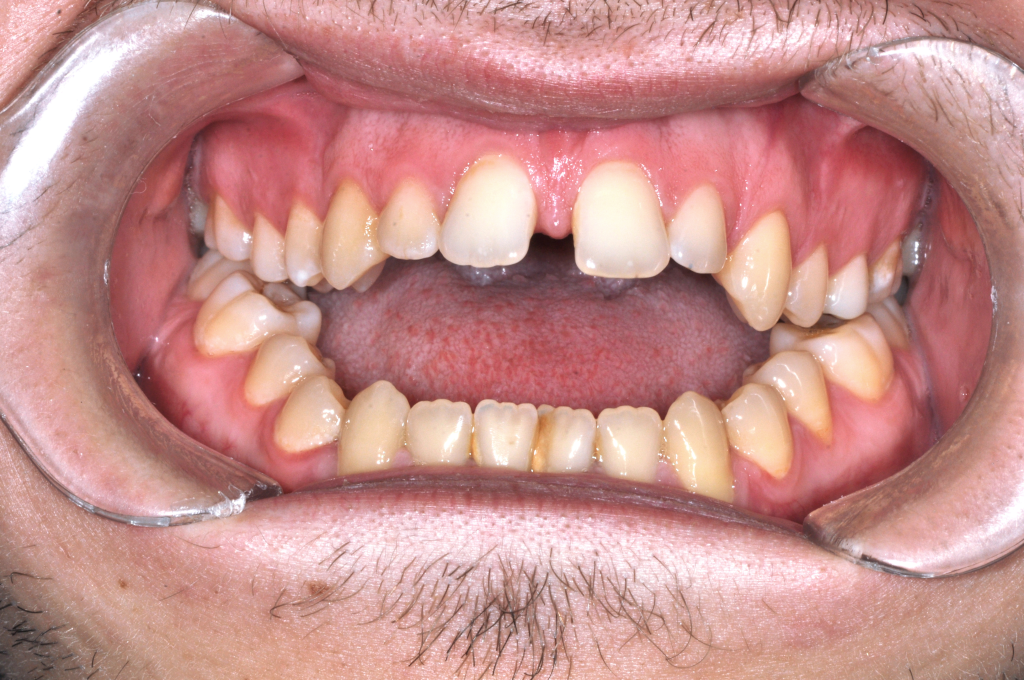

Előtte fogsor - Állcsonti aszimmetria kezelése

Ebben az esetben az arc és a harapás nem egy középvonal mentén működött.

Az alsó állkapocs oldalirányú eltérése instabil harapást és aszimmetrikus mosolyt okozott.

A probléma nem fogállási, hanem állcsonti eredetű volt.

A kezelést fogszabályozással készítettük elő, majd

mindkét állkapocs műtéti áthelyezésével szimmetrizáltuk a harapást és az arc középvonalát.

Eredmény: kiegyensúlyozott harapás, rendezett arcarányok, természetes mosoly.